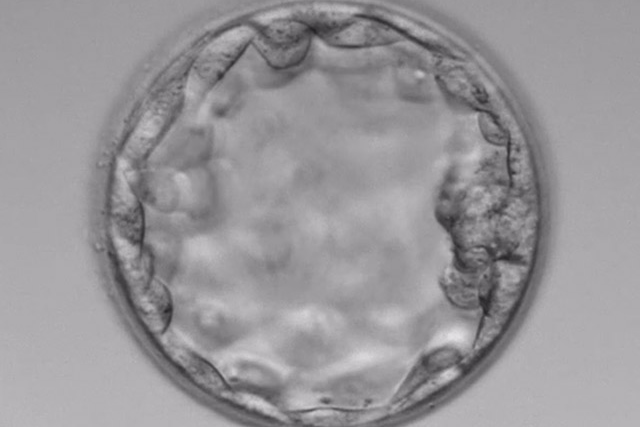

高度生殖補助医療(体外受精・胚移植・先進医療)について